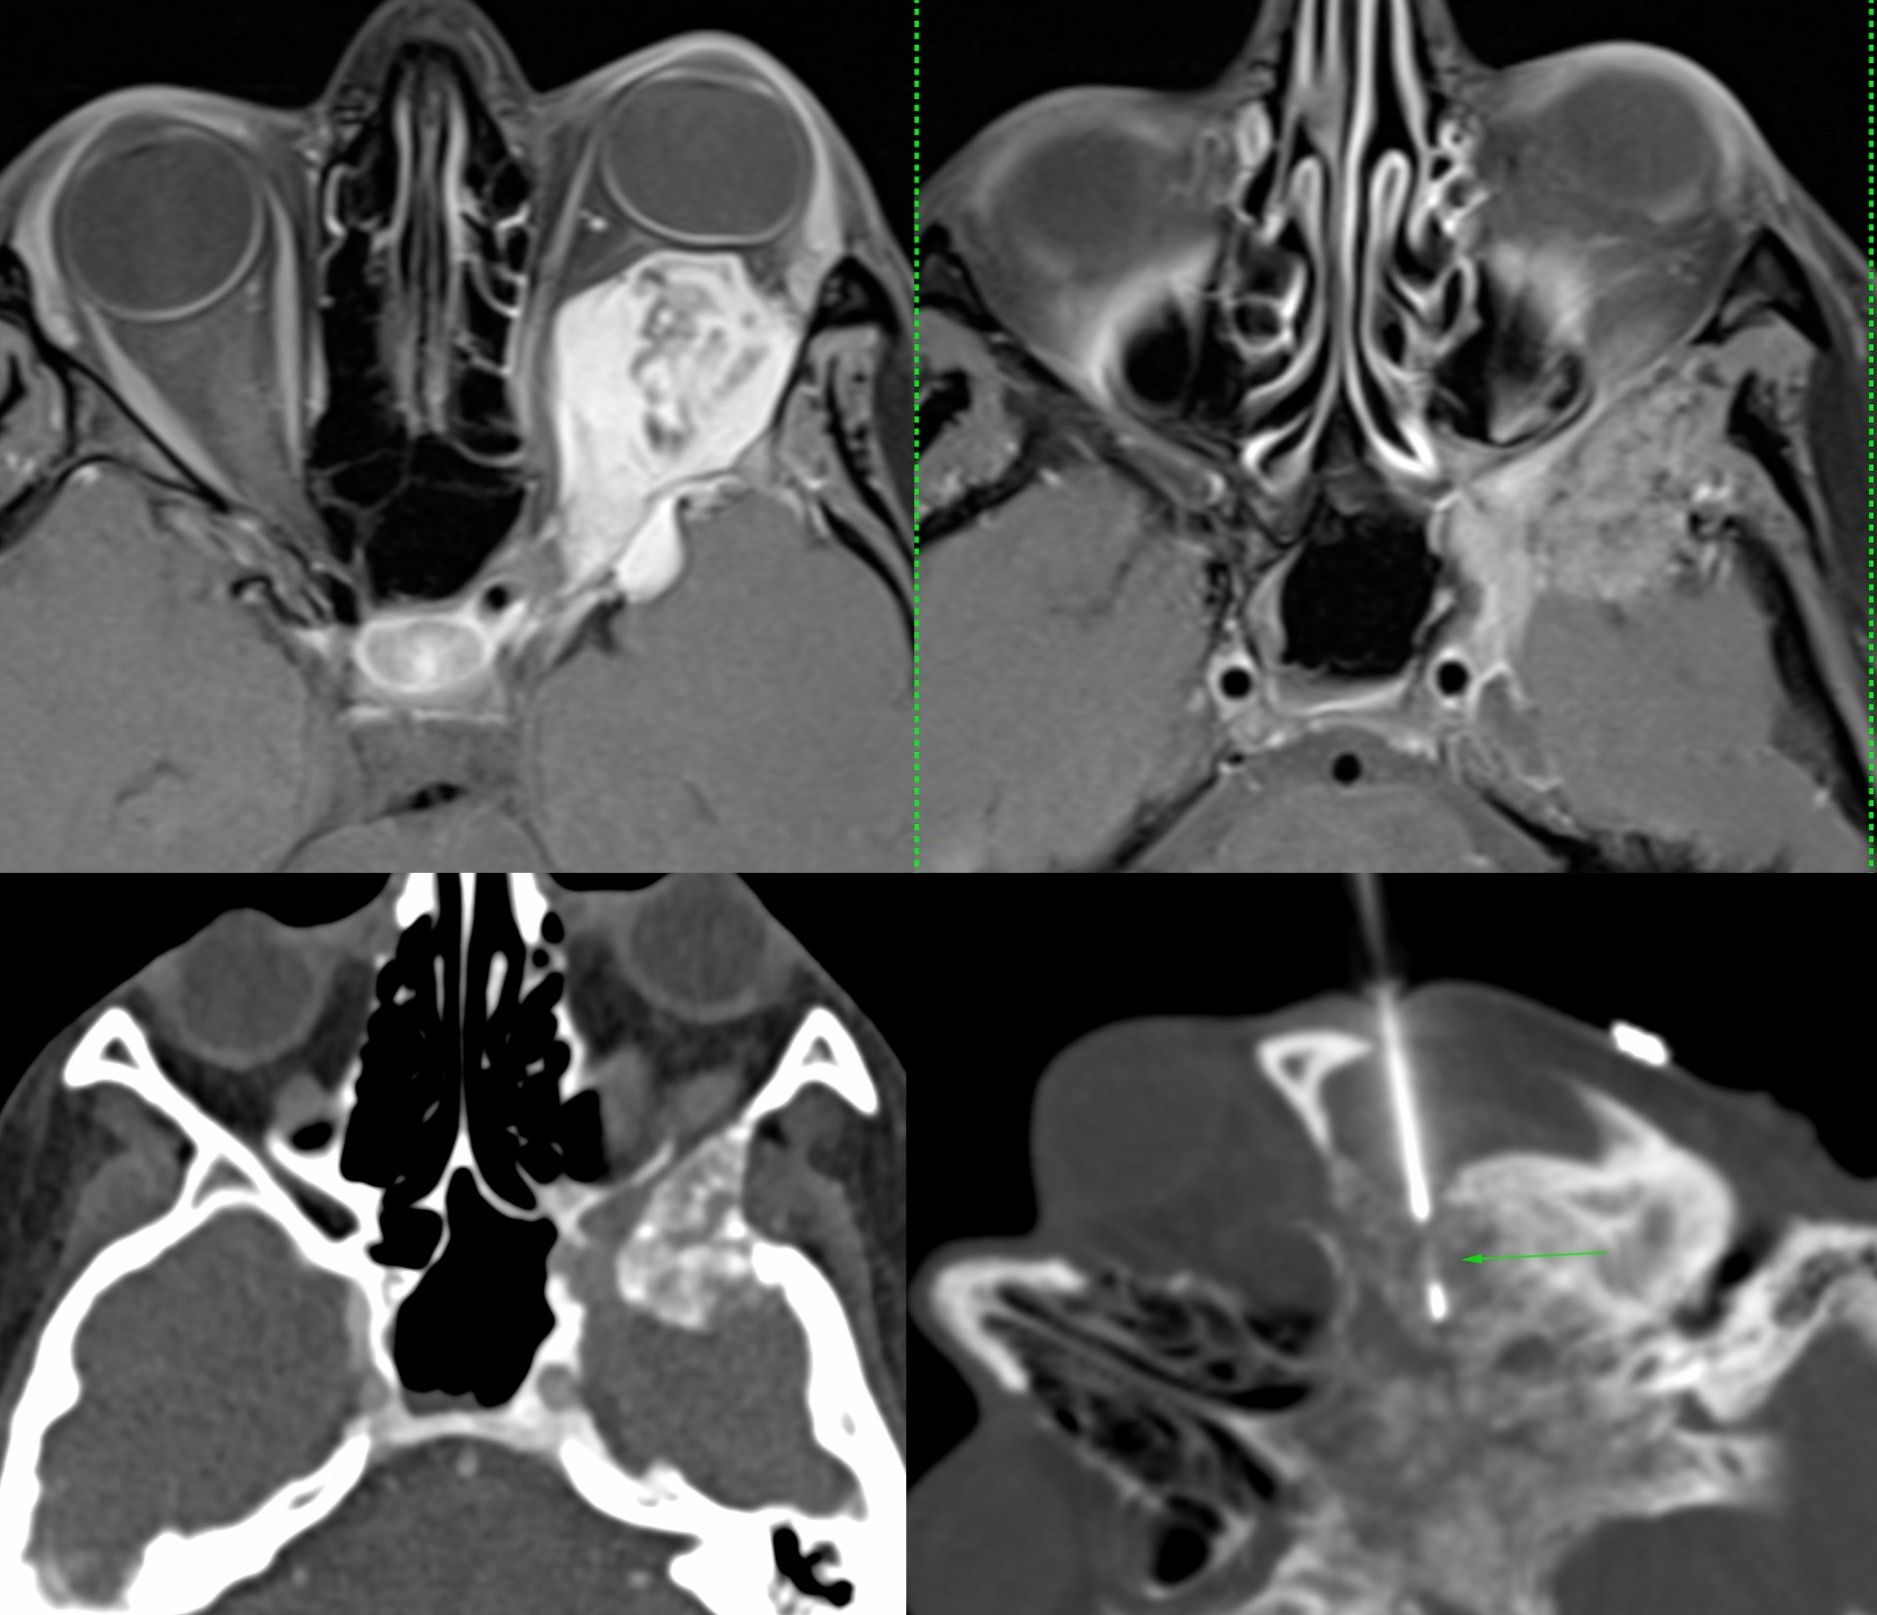

Case 23: Biopsy of Greater Wing of Sphenoid in a 25-Years Old for Recurrent Adenoid Cystic Carcinoma

Bhavin Jankharia - 15 April 2021